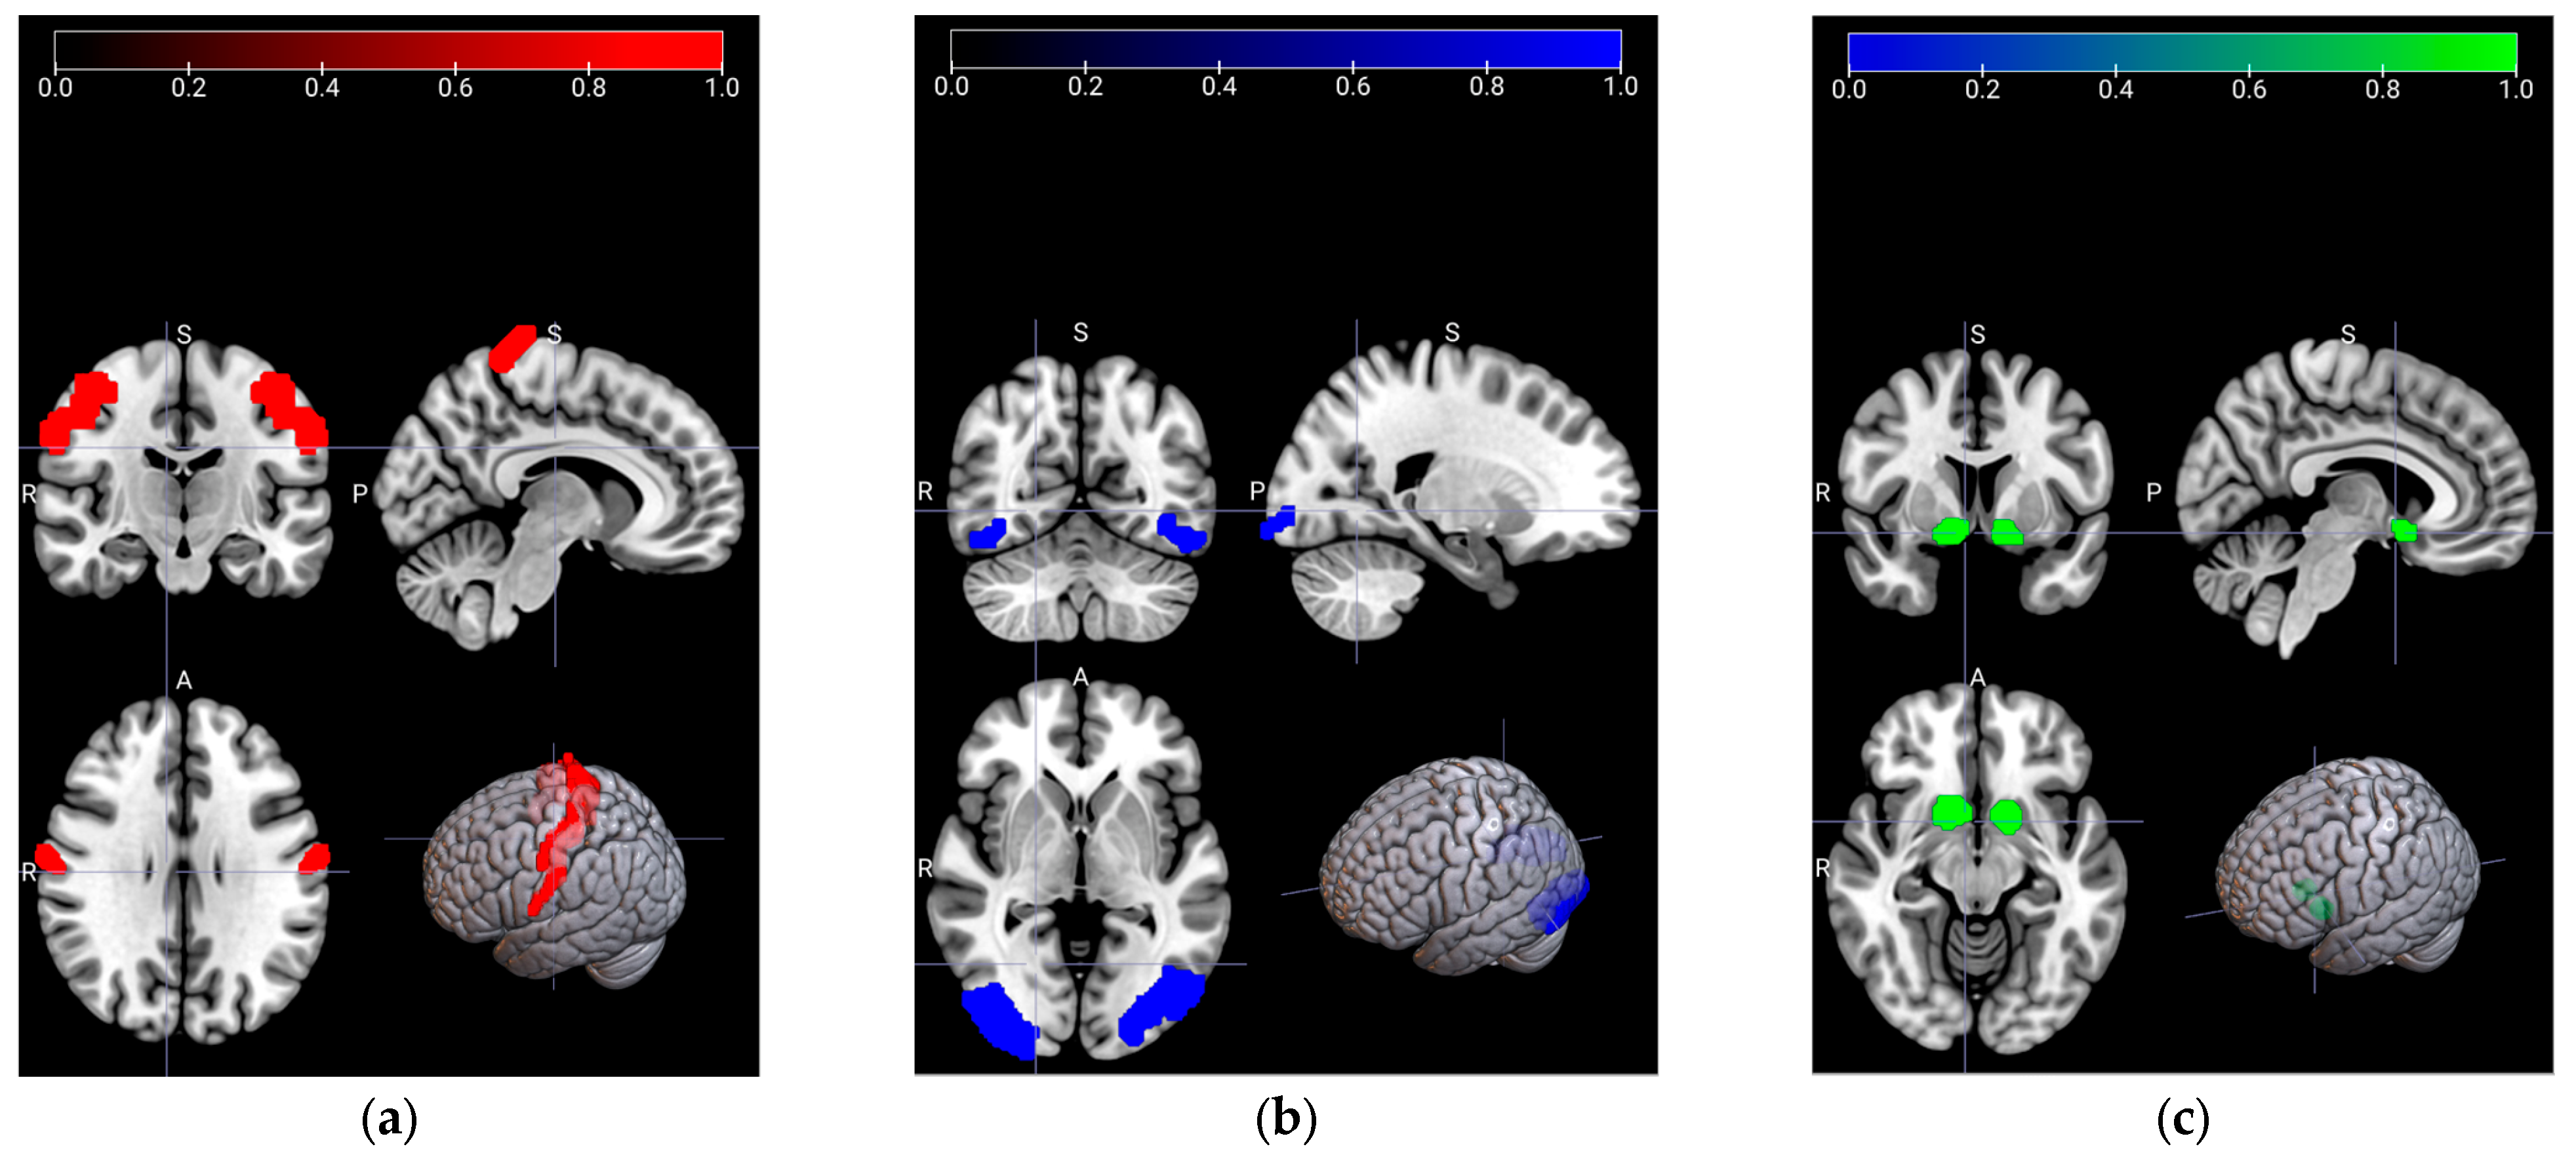

2.2. Dataset Descriptions

2.2.1. Resting State fMRI (rs-fMRI)

2.2.2. Emotion fMRI (em-fMRI)

2.2.3. Motor fMRI

2.2.4. Memory fMRI (mem-fMRI)

2.3. Signal Preprocessing

2.4. ROI Selection and Signal Extraction